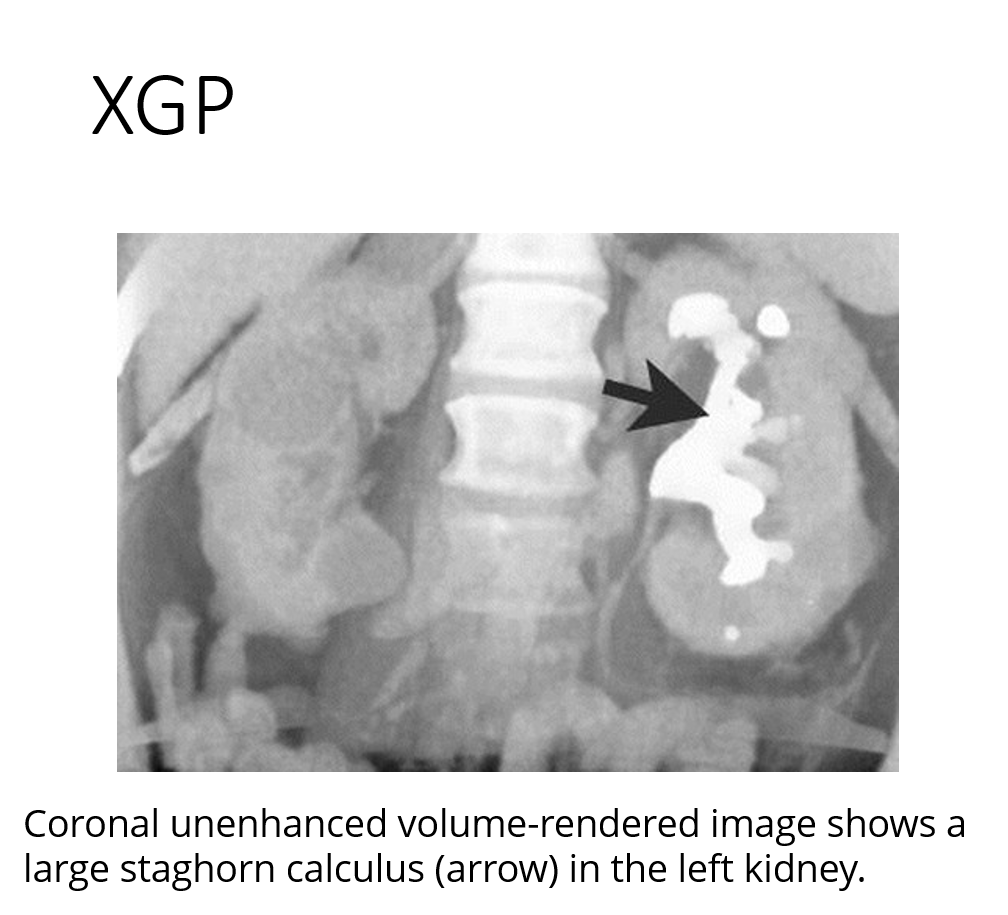

XGP with staghorn calc